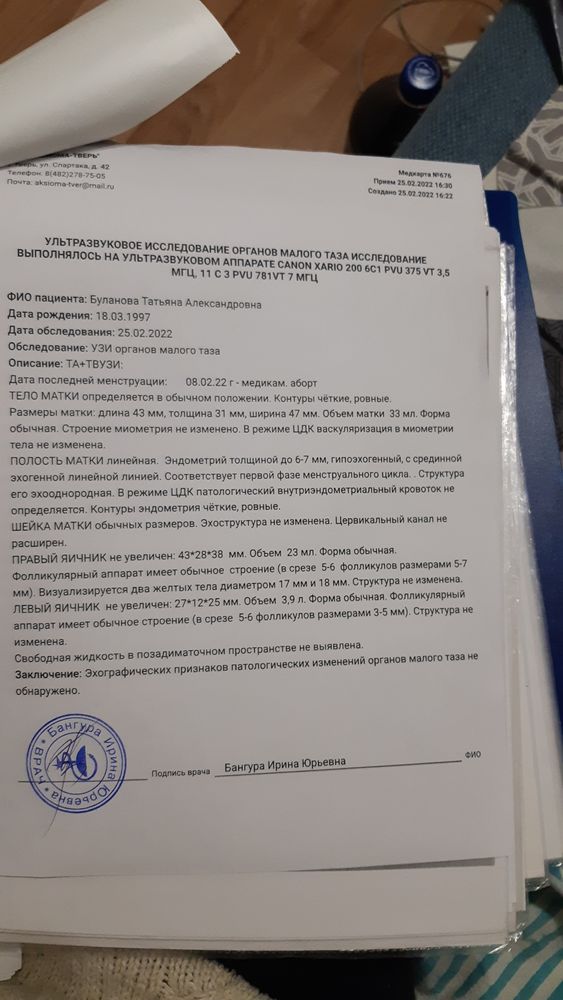

По контрольному узи, делала 2 раза все хорошо